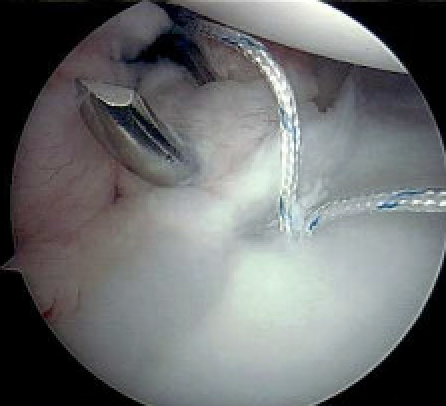

Anterior capsular plication +/- rotator interval closure

- option 1: Suture plicate capsule to labrum

- option 2: Anchors in glenoid and use to plicate capsule to labrum

Anterior capsular plication with sutures

Anterior capsular plication with suture anchors